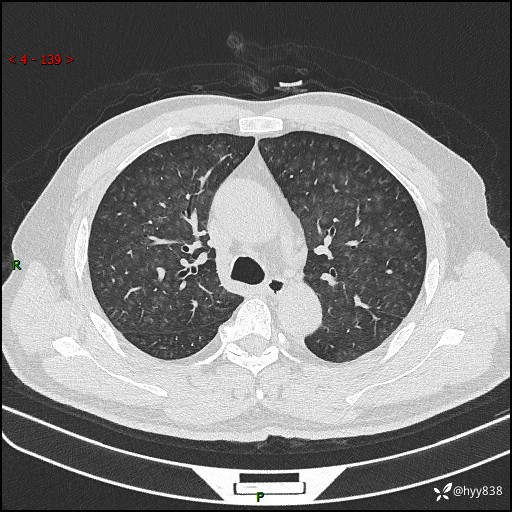

昨天肺结节门诊,“对门”呼吸科申请会诊病例,弥漫性肺部病变---结果公布~

简要病史:患者1周前无明显诱因出现咽喉部疼痛,随后出现咳嗽咳痰,起初干咳为主,后出现咳少许绿色痰,当时有发热,体温为39℃,无畏寒寒战,无胸闷胸痛,无活动后气短,无咯血,无鼻塞流涕,无全身酸痛,患者于诊所输液治疗后体温正常,但仍有咳嗽。患者3天前当地县人民医院就诊,患者仍有咳嗽,咳嗽较为频繁,咳嗽后出现头痛,伴有少许咳痰,随后出现活动后气短,1天前患者再次出现发热,体温最高为40℃,伴有畏寒寒战,伴有乏力、纳差,伴有胸闷不适,无咯血,无全身皮疹,无血尿、尿频尿急尿痛,无腹泻,诊断为“重症肺炎 感染性休克 肾功能异常 痛风”;予以抗感染(亚胺培南),抗病毒(奥司他韦)等对症治疗。患者复查胸部CT提示双肺病灶较前有所增多,建议上级医院就诊,门诊以“肺部感染”收入我科。 起病以来,患者食欲欠佳,大小便正常,睡眠、精神欠佳,体力下降、体重无明显变化。

辅助检查:CT

临床诊断:肺部感染

胸部HRCT